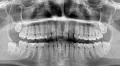

10 месяцев назад при зевке щелкнула челюсть справа, и я не смогла открыть рот более, чем на 2 см. Через 20 минут она открылась через щелчок. С тех пор щелкает, т.е. до открытия 2 см нормально, потом щелчок и открывается. Хуже того — ночью западает, если спать на левом боку. Открывается, если лечь на правую сторону на ровную поверхность.

Не так все просто, данная ситуация называется дисфункция сустава, и для начала необходимо понимать причины данного явления (причина не имеют ничего общего с зеванием, это стечение обстоятельств) и после говорить о возможном лечении.